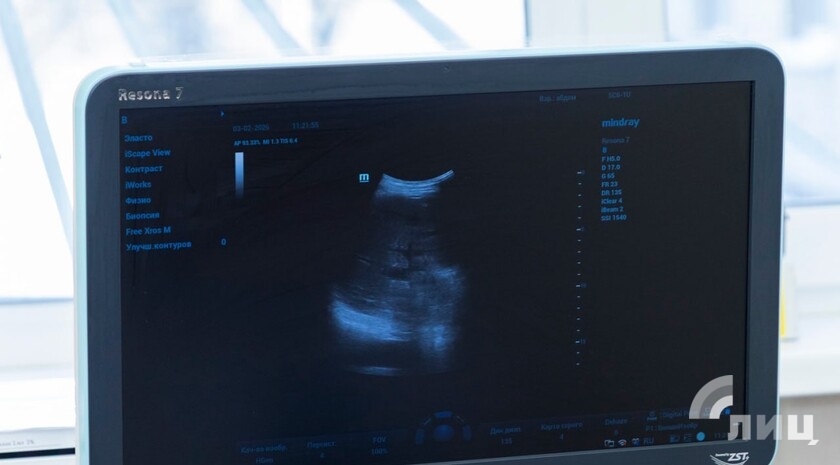

Кроме того, диспансер получил УЗИ-аппарат экспертного класса, который повышает точность выявления новообразований на ранних стадиях за счет улучшенной визуализации. Кроме того, благодаря новому 128-срезовому аппарату для компьютерной томографии луганские онкологи диагностируют болезни на ранних стадиях